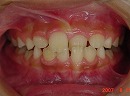

矯正前の写真を見ると、

上の前から2番目の歯だけ咬み合わせが上下逆になっています。

矯正後は、上下の咬み合わせが改善しています。

今回も治療には、独自の方法とビムラー・t4k等を利用して改善しました。

治療終了時の歯は、乳歯と永久歯が混在している為、

永久歯の歯並びについては永久歯が萌えてから、加えて改善していく計画です。

なを、顎骨のバランスは良好の為、永久歯を抜歯する必要は全くありません。